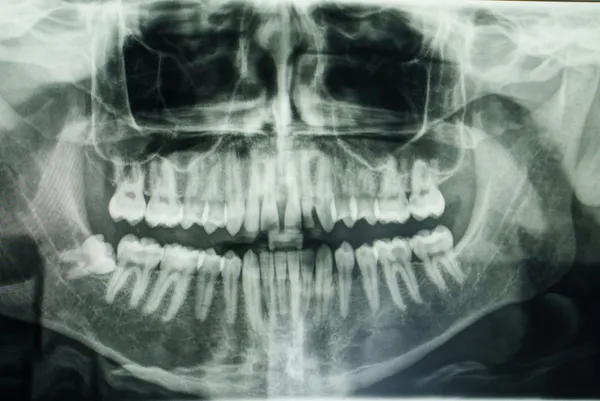

Aktaş, özellikle 20'lik dişlerin genellikle gömülü kaldığını, bu durumun daha fazla ağrıya ve çeşitli enfeksiyonlara yol açabileceğini dile getirerek, "Gömülü dişler genellikle panoramik röntgen gibi görüntüleme yöntemleriyle tespit ediliyor. Gömülü dişlerin erken dönemde fark edilmesi, ileride karşılaşılabilecek komplikasyonların önüne geçilmesini sağlar. Bu nedenle düzenli diş hekimi kontrolleri büyük önem taşır." ifadelerini kullandı.